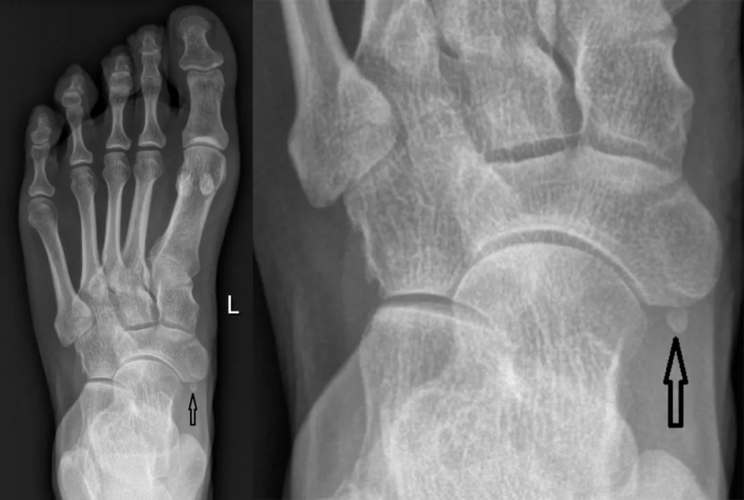

足踝撕脱性骨折与籽骨分不清楚?背下这张图再也不会漏

籽骨骨折

12种常见足踝部籽骨,小骨及变异